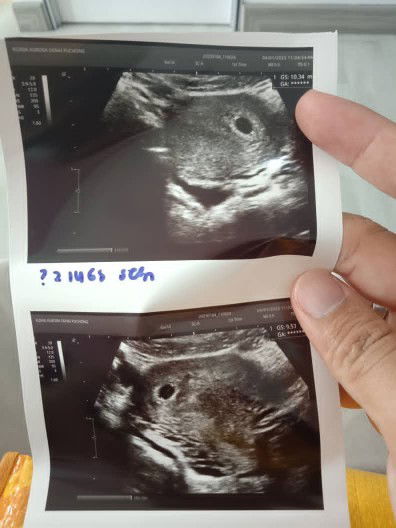

Twins atau bukan

Klu mcm ni kira twin ke mcm mna.. sbb dua kntung..d side yg brbeza

Sama ada twin atau sbb terlalu awal

berapa week scan?

msa scan ni 6w..